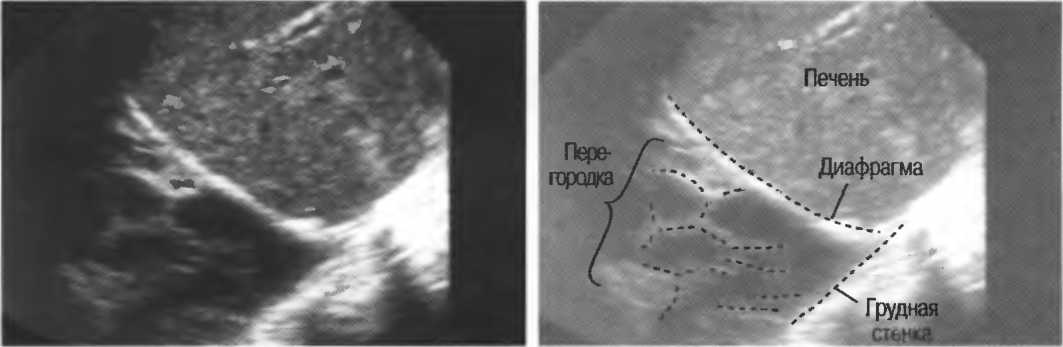

в Найроби, коллективу Найробийского рентгенологического центра;